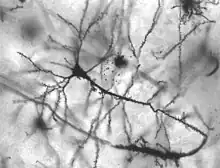

Neurons in person with epilepsy, 40x magnified